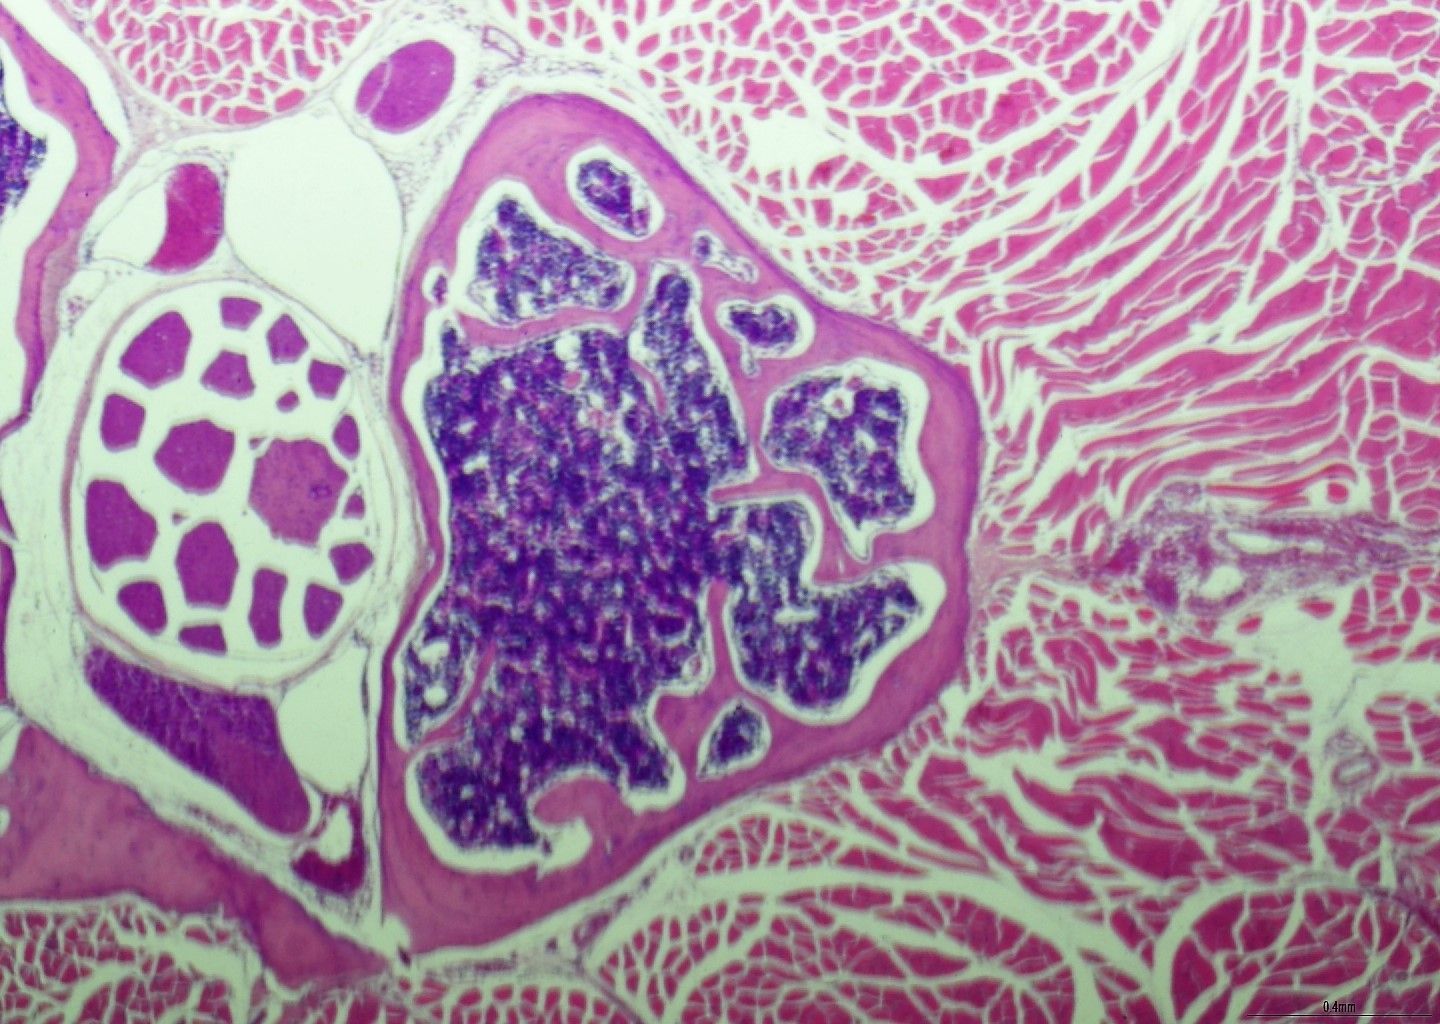

- BMT ਬਾਇਓਪਸੀ ਦੇ ਅੰਦਰ ਖਾਸ ਖੂਨ ਸੈੱਲ ਟੀਚਿਆਂ ਦਾ ਪ੍ਰਦਰਸ਼ਨ

- ਡਾਇਗਨੌਸਟਿਕ ਅਰਧ-ਪਤਲਾ ਰਾਲ ਭਾਗ

- ਅਨੁਕੂਲ ਅਤੇ ਉਪ-ਅਨੁਕੂਲ ਰੰਗਾਈ ਦਿਖਾਉਣ ਵਾਲੇ ਰੰਗ ਚਿੱਤਰਾਂ ਦੀ ਔਨਲਾਈਨ ਲਾਇਬ੍ਰੇਰੀ